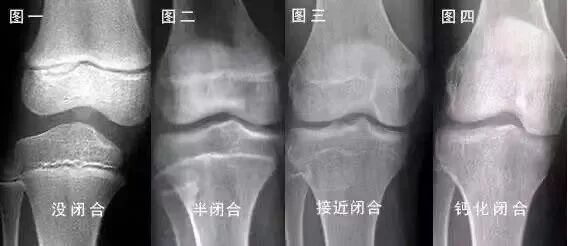

成年人有希望自然长高吗?答案是:有希望!生活中,很多人会把长高时间同年龄划等号,事实上,人能不能长高,和成年与否没关系,而是取决于双下肢的骨骺线是否闭合。而所谓骨垢线,就是指骨骺和骨干之间有一层软骨层。

如何知道自己是否还有机会长高?如果您想知道自己的骨垢线有没有闭合,照个X光片就能知道。因为,闭合前的骺板是一条透亮的区带,而闭合后透亮区消失,与旁边的骨骺融为一体。一般来说,骨骺闭合后,长骨便不再生长,人也就没法长高了!所以说,很多人在成年后依旧可以长身高,就是充分利用了成年后骨骺未闭合那几年的时间。